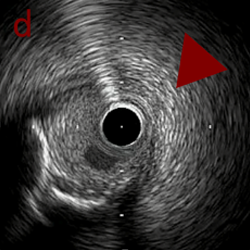

a,b,cはさらに石灰化に食い込み、石灰化量は減少。

それに伴いdではbiasがさらにtentingのIVUS所見にへんかしhigh injury riskと思われた。

引き続き造影で確認してpinpointで引きのOAS high speedを3回さらに追加のためcでIVUSマーキングを行い、その点より引きで赤線のpinpoint OAS high speedを行い、dに関してはinjury回避のためにOASを当てない方針とした。

a,b,cの十分な石灰化のsanding。

High riskのbias所見へと変わっていったdの部位に関してはpinpoint OASを行うことでinjuryなく治療できた。

OASを行うたびに徐々に心筋側側にwire bias変化をきたし、石灰化病変部に関してはそれが良い変化となっているが、distal reference (d) に関してはinjury riskの高いbias変化となっていった。